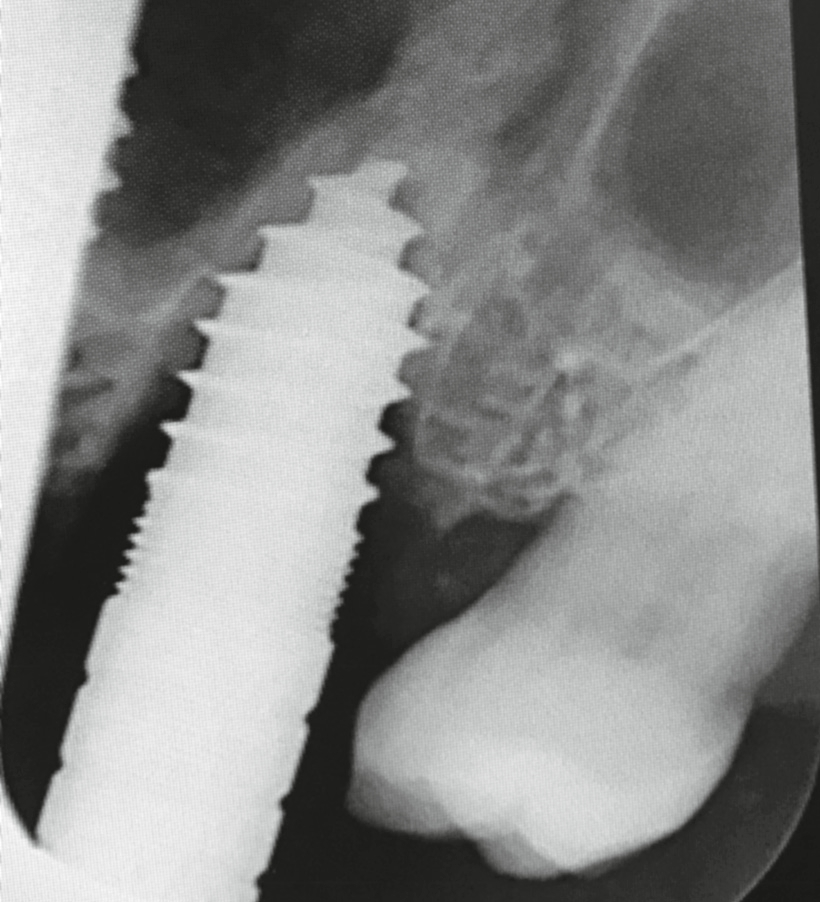

Widerwillig reifte in mir der unschöne Gedanke an einen Längsriss der palatinalen Wurzel des Zahnes 26. Die Beschwerden und der unauffällige Röntgenbefund ließen nur diese Diagnose schlüssig erscheinen. Ich wandte mich bezüglich einer erneuten Behandlung an Dr. Armin Nedjat. Nach Infiltrationsanästhesie, mittels MagicPen, entfernte Dr. Nedjat die Goldkrone. Er extrahierte den dreiwurzeligen Zahn und versuchte, in den vorhandenen Alveolarknochen, welcher durch die Trifurkation eingeschlossen war, zu implantieren. Der erfahrene Behandler benutzte zunächst den gelben konischen Dreikantbohrer. Danach erfolgte im D3- Knochen die Verdichtung des Knochens mit dem Ziel, eine Primärstabilität von 30–40 Ncm mit den Kondensern vom Durchmesser 2,4 mm, 3,0 mm, 3,8 mm, 4,3 mm zu erreichen. Nach dem Kondenser mit Durchmesser 5,3 mm war erst eine ausreichende Stabilität von 35 Ncm erzielt worden (Abb. 2). Minimalinvasiv wurde ein direkter Sinuslift durchgeführt – genial einfach durch Linkslauf des orangen Krestalbohrers vom Durchmesser 3,7 mm. Auf diese Weise kann die Schneider- Membran um bis zu 10 (!) mm angehoben werden. Ein Champions® (R)Evolution Titan-Implantat, Durchmesser 5,5 mm, Länge 10 mm, wurde inseriert (Abb. 3).